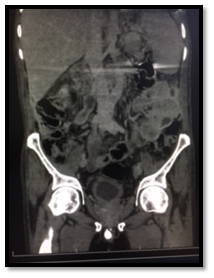

Post-operatively, The SPC was not draining well with persistent suprapubic urine leakage, so the patient was referred to our hospital 2 weeks following the primary surgery. On examination; patient was conscious, well- oriented with average general condition. Abdominal examination showed gapping of suprapubic wound with leakage of turbid urine; the SPC was not functioning well. A stone was felt in the bulbar urethra during perineal examination. Patient gave history of left nephrectomy 2 years before for a nonfunctioning kidney. Serum creatinine, BUN, HB, and WBCs were 64 mg/dl, 3.4 mmol/l , 9.9 gm, and 6640 respectively. Non- contrast CT showed no intraperitoneal fluid collection, right moderate hydroureteronephrosis, dilated left ureter with 2 stones in its lower end and 3 stones in the proximal bulbar urethra (Figure 1). Retrograde urethrocystogram showed a 3 cm stricture segment at the distal bulbar urethra and another annular stricture at the proximal bulbar urethra in addition to an urethral diverticulum in between containing the stone and grade 4 right vesico-ureteral reflux (Figure 2).

Figure 2: Antigradeurethrogram showing (1) distal bulbar uretheral stricture 2.5 cm., (2) urethral diverticulum, (3) proximal bulbar annular stricture.